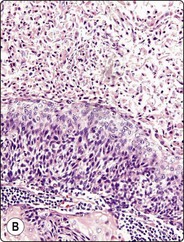

Fig. 4.9 Nasopharyngeal carcinoma (undifferentiated, lymphoepithelial type, WHO type III)

Loose clusters of undifferentiated epithelial cells with vesicular nuclei, prominent nucleoli and pale fragile cytoplasm. Background of lymphocytes. (A, MGG, HP; B, H&E, HP).

Nasopharyngeal carcinoma (NPC) is a clinicopathologic entity different from other squamous cell carcinomata of the head and neck. It is distinguished by its particular histology, geographic distribution, relationship to Epstein-Barr virus, and the absence of an alcohol or tobacco etiological relationship. A proportion of NPCs show squamous differentiation and the cytological pattern of non-keratinizing squamous cell carcinoma (squamous cell carcinoma/WHO type II) (Fig. 4.8). Keratinized cells (WHO type I) are uncommonly found. The majority of NPC are poorly differentiated or undifferentiated. Cells from undifferentiated NPC (UCNT, WHO type III) form loose clusters with no specific microarchitectural pattern, and are usually mixed with lymphoid cells. In the ‘lymphoepitheliomatous’ type (Schmincke-Regaud) the cells tend to be less cohesive, resembling Hodgkin’s disease or large cell non-Hodgkin lymphoma. However, in NPC, the malignant cells are still clustered and have more abundant pale cytoplasm contrasting with the lymphoid cells in the background (Fig. 4.9). Plasma cells are frequently found among the lymphoid cells. Immunostaining for cytokeratin and a pan-lymphocyte marker is helpful. Epstein-Barr virus-associated nuclear antigen is demonstrable by anticomplement immunofluorescence in undifferentiated tumors. Other patterns of growth may occur and may cause diagnostic problems; for example, spindle cell forms may be difficult to recognize as carcinoma.